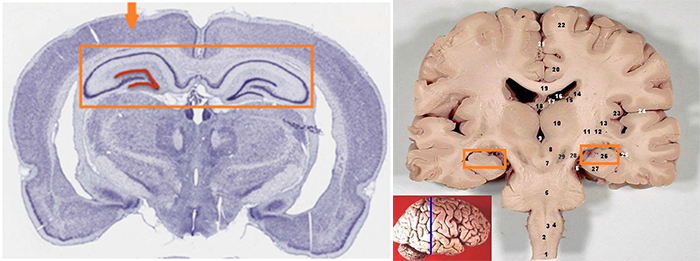

연구팀은 면역조직화학기법(immunohistochemistry)과 유전자표지 기술 등을 이용하여 신경전구세포 및 성숙한 신경세포의 표지 단백질을 정밀 분석했습니다. 그 결과, 해마의 치아이랑(dentate gyrus) 부위에서 신경전구세포가 존재하고 있으며, 일부는 새로운 신경세포로 분화하고 있었습니다.

해마는 대뇌 변연계(limbic system)의 일부로, 기억의 형성, 공간학습, 감정 조절에 핵심적인 역할을 하는 구조이다. 특히 단기 기억을 장기 기억으로 전환하는 과정에서 결정적인 기능을 수행하며, 알츠하이머병과 같은 신경퇴행성 질환에서 가장 먼저 손상되는 영역이기도 합니다.